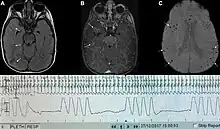

| Graph showing ataxic respirations and other pathological breathing patterns. | |